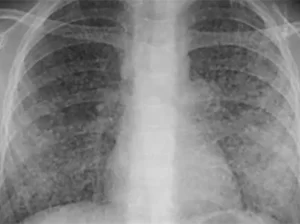

Lao phổi (Pulmonary Tuberculosis) là một trong những bệnh truyền nhiễm gây tử vong hàng...